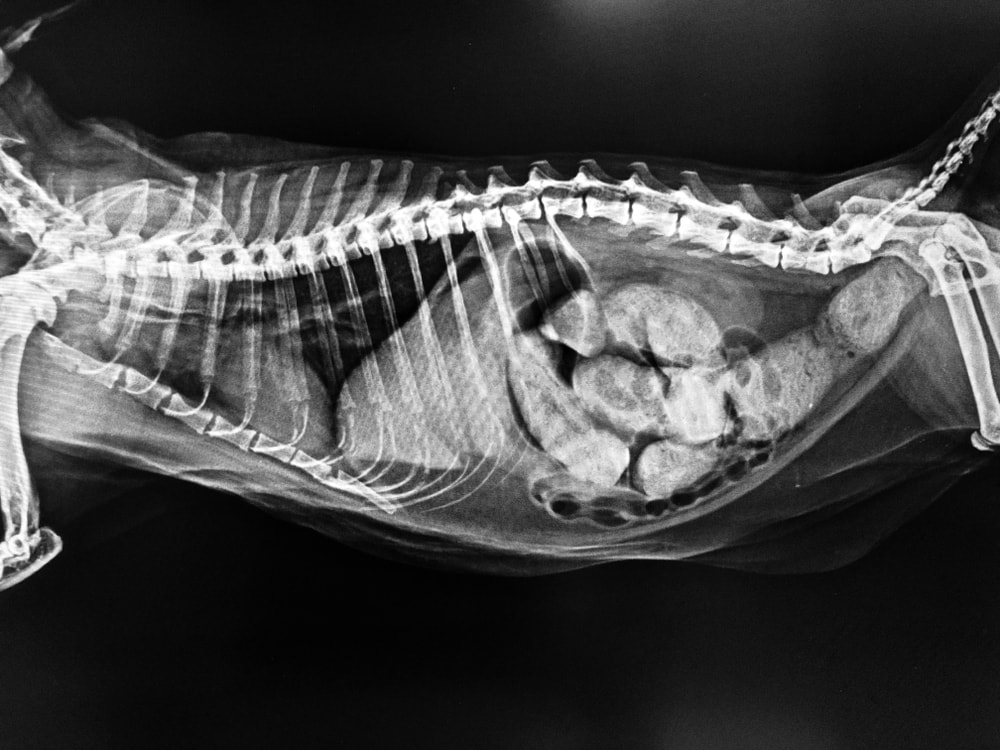

The vet will examine your cat and rule out any other medical condition that might be preventing your cat from normal excretion. The vet might request some X-rays to determine what is causing the problem. If your vet finds out your constipated cat is not under major risk and just needs some help to “unclog the pipes,” they might recommend a change of diet, prescribe more laxatives, administer an enema, or give them medication to help stimulate and regularize their digestive system. However, if your cat is obstructed or has developed a megacolon, then they might need to perform some even more invasive procedures.